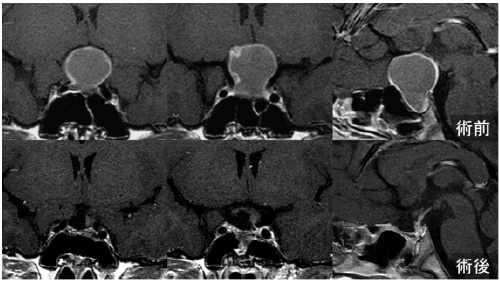

11歳女性 頭蓋咽頭腫

視力視野障害、低身長で発症しました。術前検査では成長ホルモン分泌不全が見られました。内視鏡下経鼻頭蓋底手術を行い、下垂体茎を残して摘出しました。術後、下垂体機能低下なく成長ホルモン分泌も改善しました。経過中に下垂体茎に小さな嚢胞が出現したためガンマナイフ照射を追加して経過観察中です。